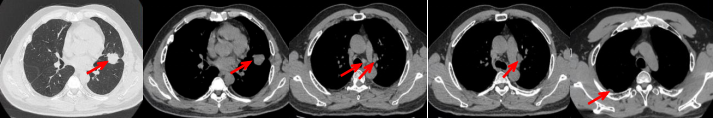

53岁男性,无吸烟饮酒史,脑血栓病史。2024年7月胸部CT:右肺下叶见一团块状软组织密度影,范围约10.8×9.0cm,边界不清,周围并见斑片状磨玻璃密度影,右肺下叶前底段支气管阻塞。纵隔及右肺门见肿大淋巴结影。考虑右肺下叶支气管肺癌。伴纵隔及右肺门淋巴结转移瘤,右下肺静脉瘤栓。2024.7.23行肺穿刺取病理:(肺)腺癌伴有神经内分泌分化。NGS基因检测:RET KIF5B exon15-RET exon12融合。PD-L1(克隆号28-8)TPS=90%。

治疗经过:2024.08开始口服赛普替尼(160mg,bid)。2024.09复查胸CT评效PR。2025.1复查胸CT:右肺下叶外基底段见一不规则形实性肿块,大小约94mm×87mm,边缘呈分叶状,其内密度不匀。右侧胸腔见少许水样密度影。评效PD,PFS=5个月。患者未同意再次组织活检,目前应用卡博替尼治疗,仍在随访中。治疗期间未出现毒性反应。

55岁男性,无吸烟史,有饮酒嗜好。2024年11月常规体检胸CT:左肺上叶占位性病变,大小约2.7×2.4cm,恶性可能大;左肺、左侧叶间胸膜及胸膜下多发微小结节,转移待除外。左侧胸腔积液,部分骨质改变。2024年12月初肺穿刺活检,病理:(肺)腺癌。NGS基因检测:CCDC6-RET(exon1-exon12)融合突变阳性(丰度:13.21%)。PD-L1表达阳性(TPS=35%,CPS=45)。

治疗经过:2025.01开始口服普拉替尼(400mg,qd)。2025.03复查胸CT:左肺上叶、右肺上叶、左肺斜裂见多发实性结节影,长径范围约3-17mm,较大者大小约17mm×12mm,位于左肺上叶下舌段,可见分叶、毛刺、胸膜凹陷、棘状突起征象。纵隔内小淋巴结。评效PR,随访中。治疗期间未出现毒性反应。

普拉替尼和塞普替尼均是新一代RET靶点选择性抑制剂,两者均能有效抑制RETV804L/M耐药突变体。相对于卡博替尼、凡德他尼等多靶点抑制剂,普拉替尼和塞普替尼对RET基因融合具有更高的选择性。本文分享的两个病例,均为RET融合突变伴PD-L1高表达的晚期肺腺癌患者一线应用选择性RET-TKIs且均快速起效,其中一例治疗有效持续时间仅5个月,另一例处于随访状态。